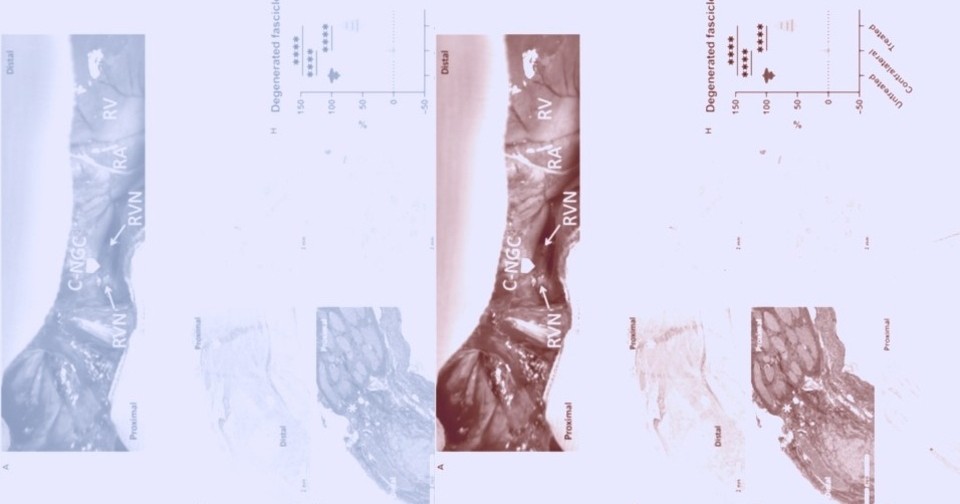

У животных из контрольной группы уже через десять дней после перерезки правого блуждающего нерва развилось смещение, или отскок, межжелудочковой перегородки в сторону правого желудочка. Такое аномальное движение перегородки нарушает синхронизированное расслабление желудочков и может свидетельствовать о нарушении наполнения левого желудочка. У минипигов после восстановления иннервации не наблюдалось отскока перегородки ни в один из моментов времени. Гистологический анализ показал, что спустя четыре месяца на пересеченных культях блуждающего нерва, помещенных в разработанную манжету, сформировался нервный мостик. Окрашивание нейрофиламентов подтвердило жизнеспособность пучков как в проксимальных, так и в дистальных культях. Восстановленные нервы сохранили физиологическое расположение пучков, аналогичное интактному контролю. Кроме того, в сердце животных из экспериментальной группы сохранялась нормальная симпатическая и парасимпатическая иннервации.